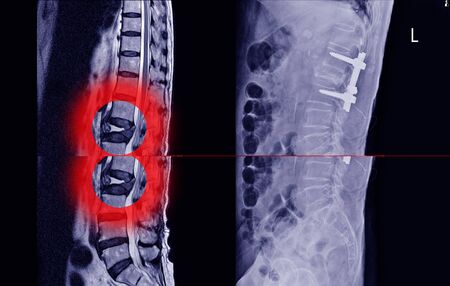

Cirugía curativa. En las ocasiones en el que el tumor primario tiene buen pronóstico y es posible quitar la metástasis por completo hay que realizar una cirugía que elimine la metástasis por completo. Se trata de cirugías muy complejas, agresivas que normalmente incluyen la retirada de una o varias vértebras al completo, siendo necesario aportar tornillos y cajas intersomáticas para recuperar la estabilidad espinal.

Estabilidad Espinal. Mantener la estabilidad espinal es primordial, como ya os hemos contado la metástasis vertebral al crecer puede destruir la vértebra generar dolor y provocar una fractura, deformidades o incluso complicaciones neurológicas. En los casos de metástasis potencialmente inestables pueden usarse corsé o realizar técnicas menos agresivas como la vertebroplastia, en los casos de metástasis inestables es necesario realizar fijaciones vertebrales.